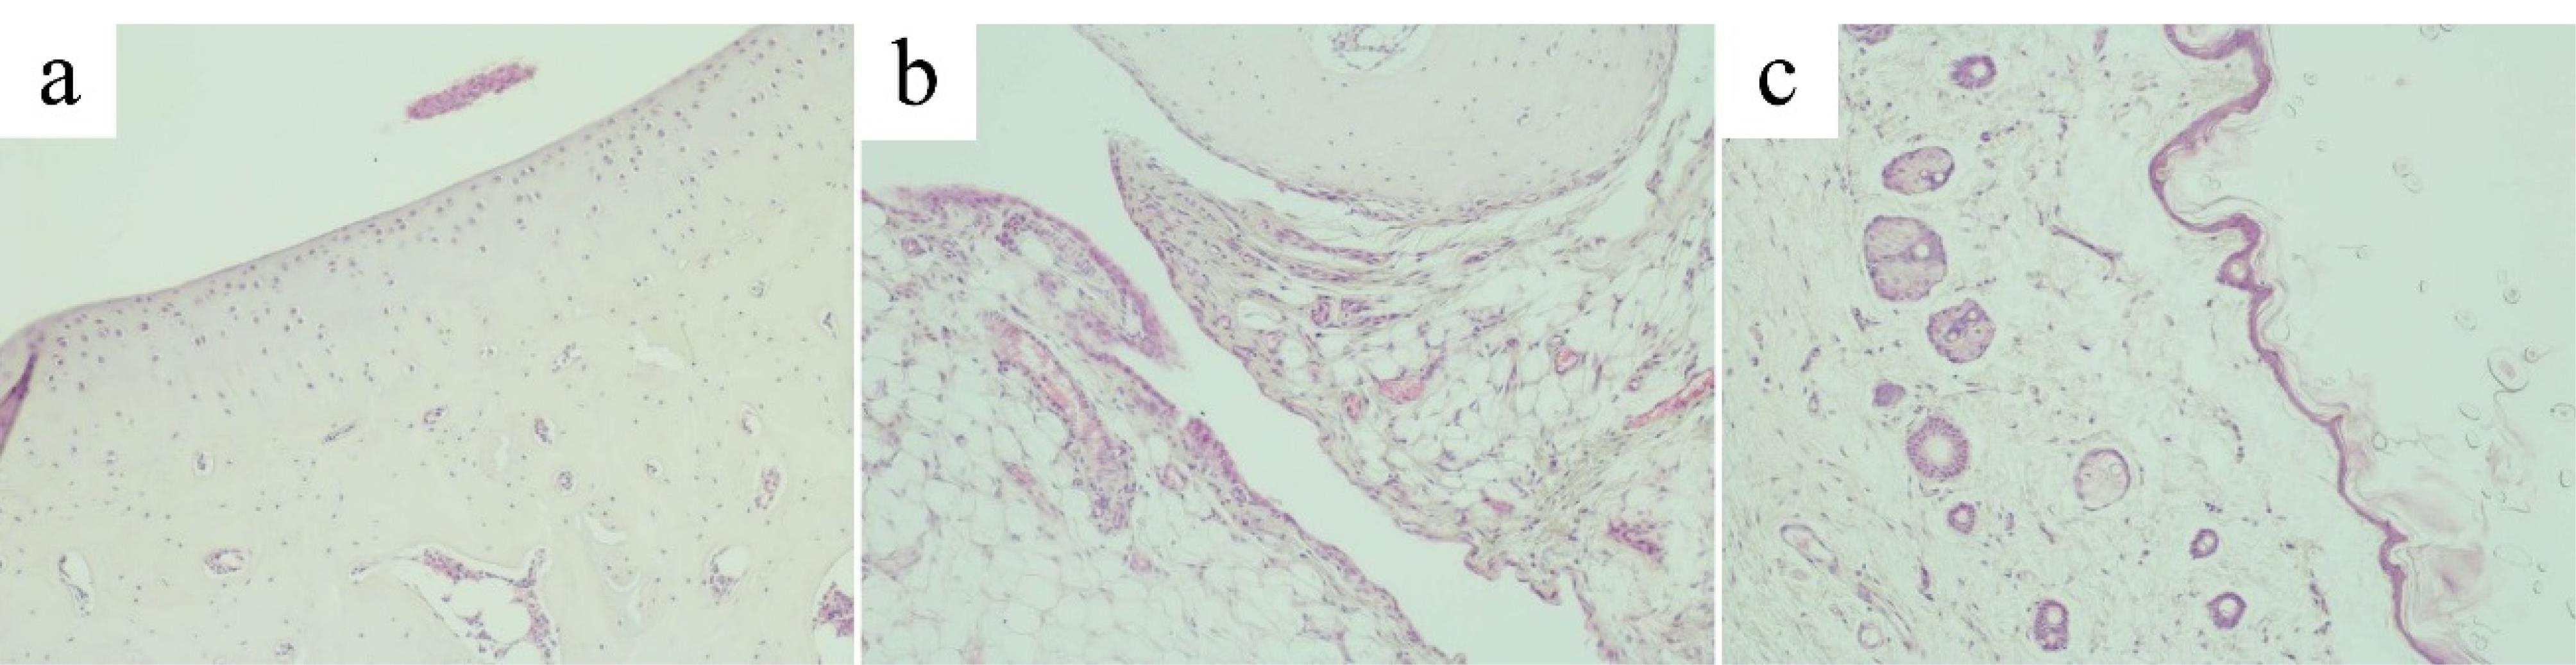

Microscopic examination of the ankle joint of the control group revealed that tissues of the joint, the synovial membrane and periarticular tissues exhibited no signs of inflammation or destruction. Articular cartilage was divided into the superficial zone, the transitional, the deep zone and the calcified zone. Small chondrocytes in the superficial zone lay in the intercellular substance at a distance from each other and mainly had a flat shape, with hyperchromatic nuclei. The transitional zone was composed of randomly organized obliquely oriented fibrils. In the deep zone, chondrocytes with basophilic cytoplasm were arranged in columns perpendicular to the articular surface. The hyaline cartilage contained no nerves or blood vessels. The calcified zone, penetrated by capillaries, consisted of calcified cartilage with a more intensely colored intercellular substance and chaotically scattered groups of small hyperchromic chondrocytes (Figure 6a). From the inside, the articular surface was lined with an areolar type synovial membrane penetrated by blood and lymphatic vessels and nerve fibers. The synovial folds protruded into the joint cavity. Synovial cells were densely arranged, sometimes in several layers (Figure 6b). The periarticular tissue of rats in the control group exhibited no signs of inflammation (Figure 6c).

Figure 6.

Articular cartilage, synovial membrane and periarticular tissues of the control group. (a). Articular cartilage of the ankle joint of the control group (original magnification х100). (b) Synovial membrane of the ankle joint of the control group (original magnification х100). (c) Periarticular tissue of the ankle joint of the control group (original magnification х100)